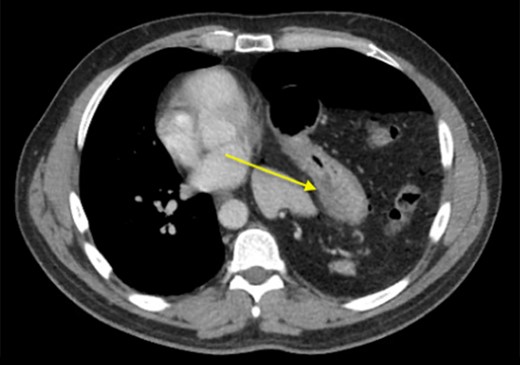

We present a 44-year-old male patient came to the emergency department complaining of right upper quadrant abdominal pain. The patient reported taking over-the-counter (OTC) ibuprofen intermittently for a past few months due to backaches. His past medical history is only positive for falling off a 15 feet ladder at the age of 15 years old. Upon examination, he had right upper quadrant abdominal tenderness, a heart rate of 90 beats/min and a respiratory rate of 20 breaths/min on room air. The patient clinical status was stable and looked well. Chest x-ray showed a moderate left hemidiaphragm elevation with bowel contents overlying the left chest (Fig. 1). Of note, a large amount of air inferior to the right hemidiaphragm was indicative for pneumoperitoneum. Laboratory investigations were immediately carried out and revealed a white blood cell count (WBC) of 4.5 × 109/L (normal range: 4–11 × 109/L). The WBC remained at the normal level until the end of the patient’s admission. Further imaging studies were ordered due to the peculiar coexistence of x-ray findings and stable clinical status. The computed tomography (CT) scan showed a contracted left lung with severe volume loss and just mild aeration of the left upper lung (Fig. 2). No definite left pneumothorax was seen. The majority of the left hemithorax was filled with abdominal contents including the stomach, spleen, pancreatic tail, left kidney, splenic flexure of the colon, and small bowel loops. A small hypodense focus was observed within the intra-thoracic stomach and extended to the stomach wall, with mild adjacent stranding of fat and a small amount of free fluid. We suspected the presence of perforated gastric ulcer secondary to non-steroidal anti-inflammatory drugs (NSAIDs) usage. The upper gastrointestinal (GI) series was performed and did not show any extravasation, indicating that there was some other source or the gastric perforation had walled off. The patient was thus managed conservatively; his diet was advanced and the patient discharged home on Day 4.

CT scan showing collapse of left lung and left diaphragmatic hernia.